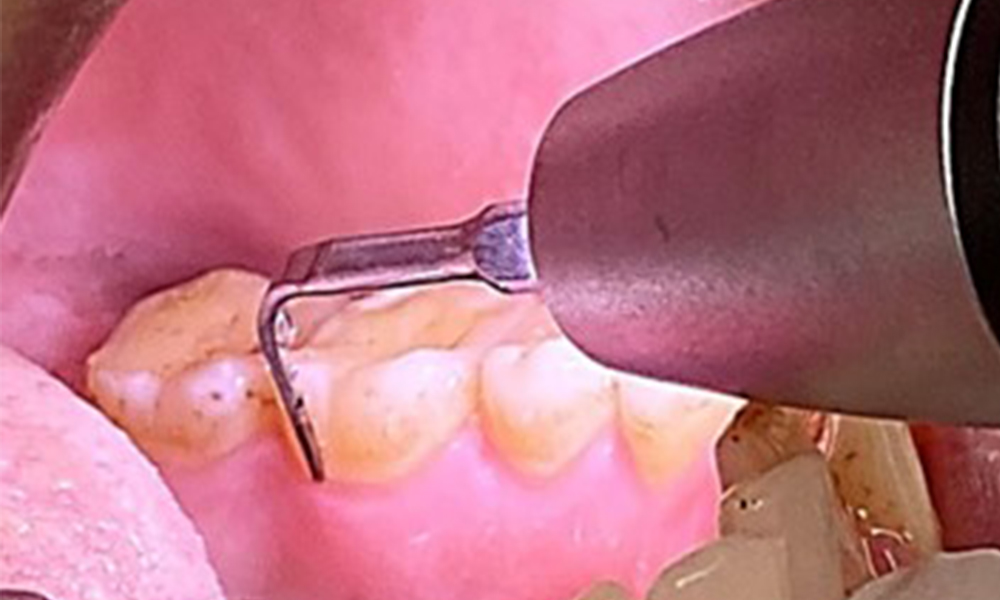

Aufgrund des guten allgemeinmedizinischen Zustandes ist der aus der Mundgesundheit ermittelte Bedarf maßgebend für die Behandlung. Die regelmäßige Erhebung der Sondierungstiefen ist unabdingbar. Die gingivale Blutung ist bei Rauchern herabgesetzt, weswegen die klinische

Diagnose einer Parodontitis nur durch Sondierung möglich ist (Abb. 7). Die ausschließliche Erhebung von Blutungsindizes verdecken unter Umständen das Bild einer bestehenden Parodontitis oder Gingivitis. (5)